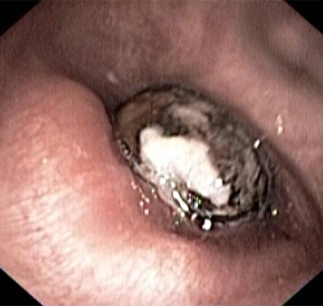

• Bronchoscopy to search for endobronchial pathology.

[Figure caption and citation for the preceding image starts]: Chest CT with presence of signet ring on left in a patient with bronchiectasisFrom the personal collection of Dr S.M. Bhorade, University of Chicago Medical Center [Citation ends].com.bmj.content.model.assessment.Caption@769db40d[Figure caption and citation for the preceding image starts]: Chest CT with dilated and thickened airways and peripheral tree-in-bud pattern in a patient with bronchiectasisFrom the personal collection of Dr S.M. Bhorade, University of Chicago Medical Center; used with permission [Citation ends].com.bmj.content.model.assessment.Caption@5d8c3fb7[Figure caption and citation for the preceding image starts]: Chest CT showing idiopathic pulmonary fibrosisFrom the personal collection of Dr J.C. Munson, Center for Clinical Epidemiology and Biostatistics, University of Pennsylvania School of Medicine [Citation ends].com.bmj.content.model.assessment.Caption@43159570[Figure caption and citation for the preceding image starts]: Chest CT of a patient with amiodarone pulmonary toxicity, showing asymmetrical opacities with a peripheral distributionFrom the personal collection of Dr A. Pataka and Professor P. Argyropoulou, Aristotle University, Thessaloniki, Greece [Citation ends].com.bmj.content.model.assessment.Caption@33fbbbbd[Figure caption and citation for the preceding image starts]: CT of the chest with intravenous contrast material showing complete left lower lobe collapse with a radiopaque object within the left lower main bronchus surrounded by a halo of airBMJ Case Reports 2008 (doi:10.1136/bcr.06.2008.0013). Copyright 2008 BMJ Publishing Group Ltd [Citation ends].com.bmj.content.model.assessment.Caption@72dca222[Figure caption and citation for the preceding image starts]: Bronchoscopy image showing a loquat seed completely occluding the bronchus intermediusFrom the personal collection of Dr S. Murgu and Dr H. Colt, University of California at Irvine Medical Center [Citation ends].com.bmj.content.model.assessment.Caption@18215d6d